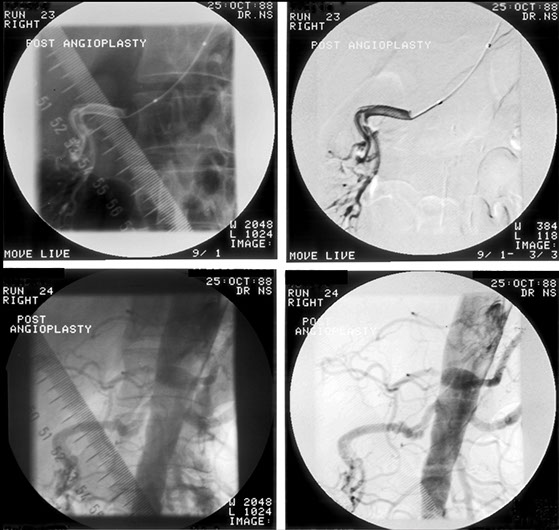

The most favourite subspecialty was angiography and interventional work particularly in the vascular field. This was the first angioplasty performed in the department. This represents atheroma with a focal stricture of the left femoral artery which was dilated with the presented result. Note that the atheromatous process is not limited to one area.

Femoral artery stricture post dilatation. Note the ragged appearance of the dilated atheromatous plaque.

This patient developed several strictures two years apart. This one is a popliteal stricture.

Popliteal stricture post dilatation

And this represents the second stricture two years later in the left lower femoral artery

And this is the post-dilatation image of the femoral stricture.